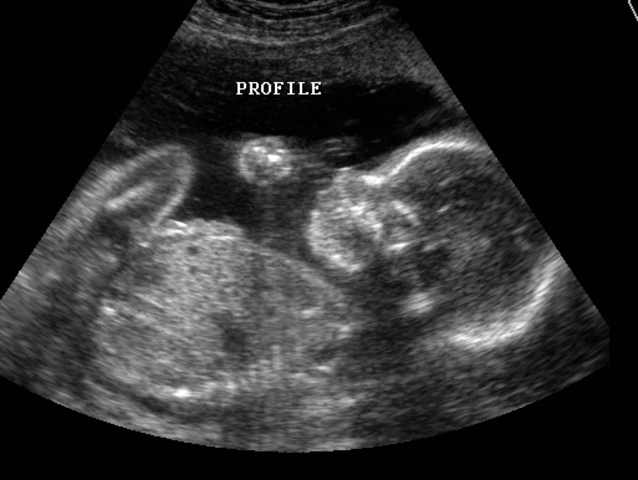

• Healthy Prenatal Experience

Healthy Prenatal Experience

My mother kept healthy habits during her pregnancy with me. She did not drink, smoke, or intake excessive unhealthy foods. These conscience choices were made to avoid risking any complications. This lead to my healthy status at birth and no health problems in my life.

• Midwife

During my mother's pregnancy she had the help pf a midwife. This was a luxury that helped my mom stay informed of usual stages of pregnency. Her midwife was a helpful resource for any questions or concerns that my mother had. This was helpful as an informed mother is usually a sign of concern for their child and later on a good sign for creating trust.